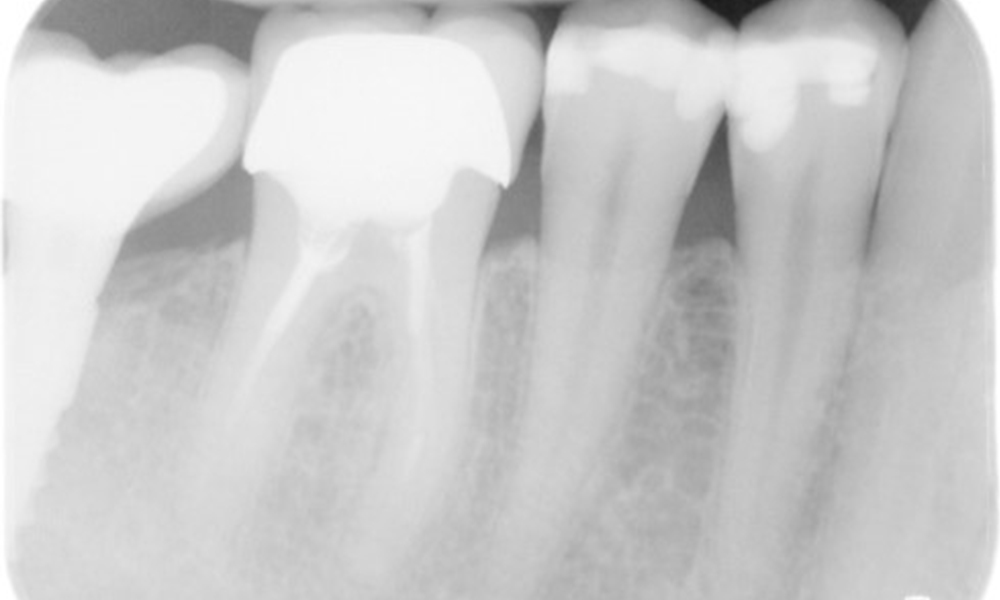

Der Patient hat einige zahnärztliche Restaurationen und zwei Implantate (2. und 4. Quadrant). Anhand der aktuellen Befunde lässt sich eine Gingivitis bei stabilem parodontalen Zustand am reduzierten Parodont (Stadium III, Grad A) feststellen.

Versorgungen: zahnärztliche Restaurationen (NEM keramisch verblendet), zwei Implantate (2., 4. Quadrant)